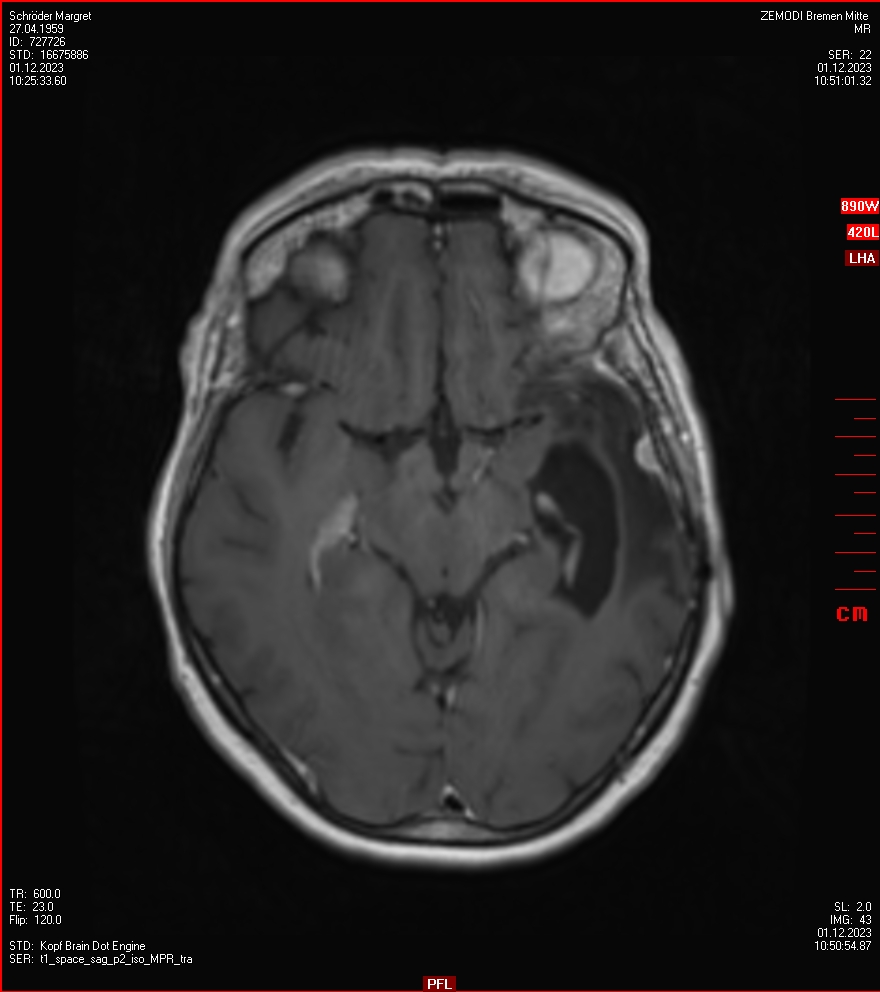

Die letzten drei Bilder Zeigen aus meiner Sicht den Tumor, der im Jahr 2021 bestrahlt wurde.

Zum Vergleich nun auch die Bilder vom 1.12.2023:

Ich denke, in den letzen 12 Monaten sind da ein paar Rezidive gewachsen,  vor 12 Monaten waren sie auch schon zu erkennen - vorher noch nicht. Nun hoffe ich auf den Rat des Spezialisten. Hoffendlich kann man etwas machen.